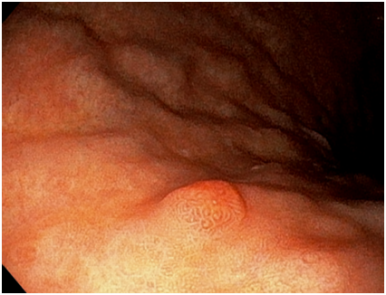

왼쪽 윗배(좌상복부)에는 비장(지라), 췌장(일부), 위, 신장, 좌측 폐 하부, 대장(비장만곡) 등 여러 장기가 밀집해 있어 정확한 진단 없이는 원인을 쉽게 알기 어렵고, 치료 시기를 놓치면 내출혈, 췌장염 악화, 장기 파열 같은 심각한 상황으로 번질 수 있습니다.

이 부위의 통증은 다음과 같은 다양한 원인으로 발생할 수 있습니다: 이처럼 원인이 매우 다양하고 복합적이기 때문에, 통증의 양상과 동반 증상만으로 자가 진단하기는 어렵습니다.